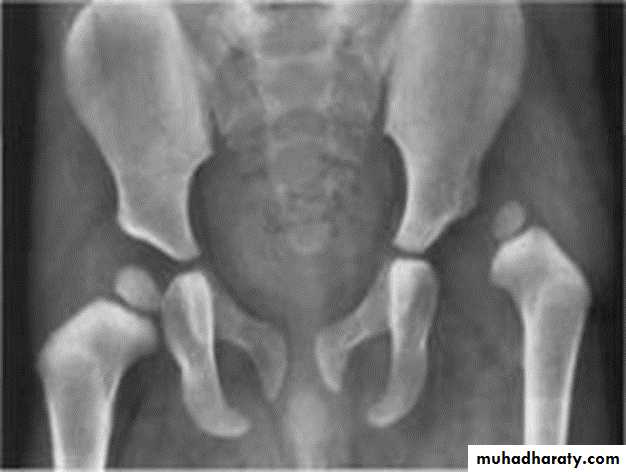

DEVELOPMENTAL DYSFLASIA OF HIP (CONGENITAL DISLOCATION OF THE HIP)

An abnormally lax joint capsule allows the femoral head to fall out of the acetabulum, leading to deformation.

Predisposing factors for the development of CDH are:

* Abnormal ligamentous laxity (effect of estrogen; fema1e:male = 6:l)

* Acetabular dysplasia .

CDH occurs most commonly (70%) in the left hip. Bilateral involvement is seen in 5%.

Radiographic features:

US (commonly used today) at 1-3 months

* Normal femoral head is covered at least 50% by acetabulum , In CDH < 50% of femoral head is covered by acetabulum .

Plain film

At 3-6 months :

By doing special veiw (Von Rosen veiw )by abduction of the thigh 45 degree and internal rotation .

In DDH the lines that drown through the femura will meet in higher level than the normally should at lumbosacral joint .

6 months and later

* AP veiw ( femural epiphysis are visualized ):* Superolateral displacement of proximal femur (disturbed shenton’s line )

* Increase in acetabular angle

* Small capital femoral epiphysis

Femoral head is located lateral to Perkin's line

* Other features that are sometimes present

Abnormal sclerosis of the acetabulum

Shallow acetabulum

Formation of a false acetabulurn